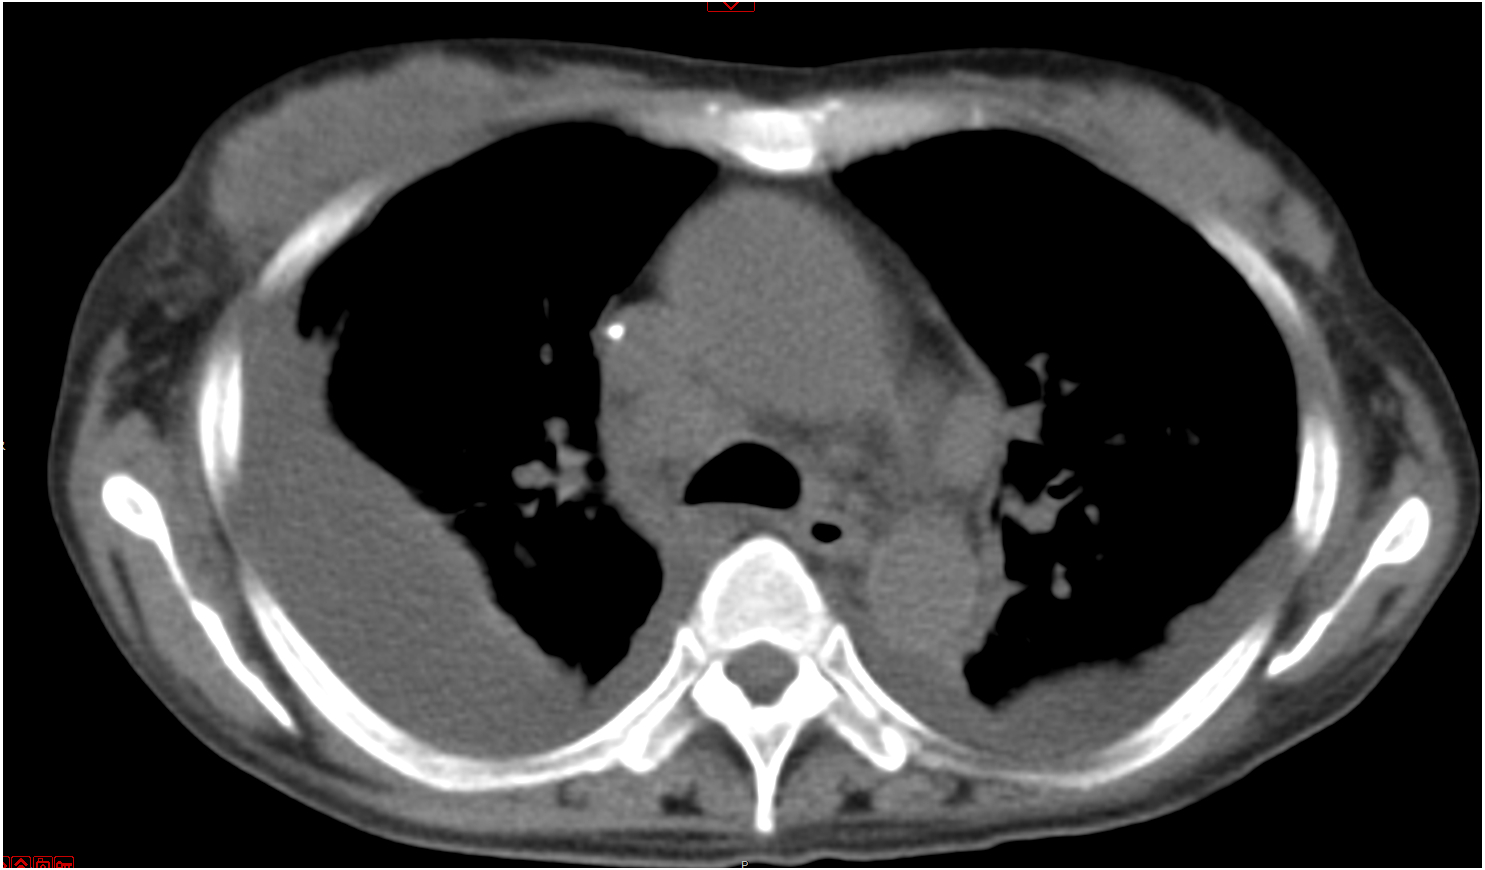

经过上述激素联合免疫抑制剂方案治疗,患者病情无改善,再次出现“发热、咳嗽”加重而就诊于当地医院,考虑肺部感染予泰能及莫西沙星静滴治疗11 d,效果欠佳并加重,鼻导管吸氧下动脉血氧饱和度仅及92%左右,故于2020-01-17转入本院ICU二科进一步诊治。入室时神志清晰,检查合作,浅表淋巴结未触及,腹软,上腹压痛。入室检查:血常规WBC 6.09×109,RBC 3.94×1012,Hb 107 g/L, PLT 33×109。总蛋白51.4 g/L,白蛋白24.16 g/L,总胆红素43 g/L,丙氨酸氨基转移酶339 U/L,门冬氨酸氨基转移酶191 U/L,肌酐34.87 umol/L,胆碱酯酶1346 U/L,降钙素原3.28 ng/mL,C反应蛋白193.5 mg/L,免疫指标阴性。D-DII 18 240 ng/mL,PT 17.1 s,APTT 42.8 s,FIB 5.08 g/L。CD4/CD8 > 1.25∶1。胸部CT示双肺间质广泛增厚并见多发斑片影,双肺肺门及纵隔见增大淋巴结,较图 2中影像增大、部分融合,见图 3。

| 图 3 2020-01-18 CT检查影像示纵膈的改变 |